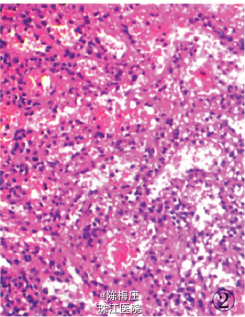

初步诊断:子宫肌瘤,子宫腺肌病,盆腔多发肿物性质待查。 确定诊断:盆腔腹膜脾组织植入。 完善相关检查,行全子宫切除术。病理检查:眼观:全切子宫1个,13 cm×8 cm×5.5 cm大小,子宫做多个切面,在肌层内查见2个大小不等灰白色肌瘤,肌瘤面积O.3 em×0.2 cm—l cm×0.66cm,肌瘤切面质韧,灰白色,呈编织状,边界清;内膜光滑,厚0.2—0.3 em,肌层厚2.5—3.5 cm,部分呈海绵状,子宫颈光滑,切面质韧,质地较细。盆腔内不规则肿物1个,灰红色,表面结节状,11cm×7.5 cm×3.5 cm大小,做多个切面,切面见多个结节,结节面积:0.4cm×0.3 cm~4.3 cm×2.5 cm,结节切面质脆,灰红色,质地细,结节边界清。另送圆形结节5个,直径1~3 cm不等,切面性质同盆腔较大肿物,均有包膜(图1)。镜检:患者子宫检查为子宫肌瘤,子宫腺肌病,病变无特殊性。盆腔多个肿物病变性质基本一致,为扩张血窦样组织,窦腔内充满红细胞,似脾红髓淤血(图2),在血窦样组织间有大小不等、发育良莠不齐的白髓样结节,结节较大者有小中央动脉(图3),结节较小者中央动脉不明显,内皮细胞无异型性,细胞分化均无异性,无病理性分裂象。可见玻璃变性纤维结缔组织似脾小梁样结构(图4)。免疫表型:血窦样内皮细胞nFli-1强阳性(图5),CD31弱阳性;CD34肿物小血管强阳性而血窦内皮细胞阴性(图6),CR和SMA均阴性;Ki-67增殖指数为5%。